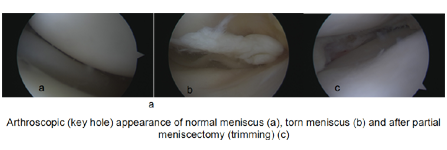

Knee arthroscopy is one of the most commonly performed surgical procedures. In it, a miniature camera (arthroscope) is inserted through a small puncture hole (portal). The camera allows for detailed examination of the knee. Your orthopaedic surgeon inserts miniature surgical instruments through other portals to confirm the type and location of the tear. Once he has done so he will either trim or repair the tear.

Partial meniscectomy: In this procedure, the damaged meniscus tissue is trimmed away. This procedure will make sure there are no loose/ unstable parts of meniscus within the joint and hence reducing pain.

Meniscus repair: Some meniscus tears can be repaired by suturing (stitching) the torn pieces together. Whether a tear can be successfully treated with repair depends upon the type of tear, as well as the overall condition of the injured meniscus.